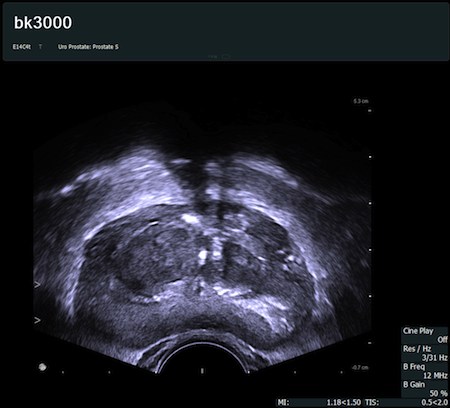

Fot. Poprzeczny przekrój gruczołu krokowego uzyskany głowicą transrektalną E14C4t.